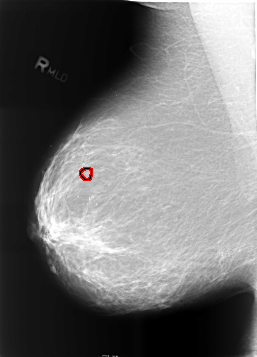

B_3465_1.RIGHT_MLO

RIGHT_MLO LINES 5712 PIXELS_PER_LINE 4104 BITS_PER_PIXEL 12 RESOLUTION 50 OVERLAY

FILE: B_3465_1.RIGHT_MLO.OVERLAY

TOTAL_ABNORMALITIES 1

ABNORMALITY 1

LESION_TYPE CALCIFICATION TYPE AMORPHOUS-PLEOMORPHIC DISTRIBUTION CLUSTERED

ASSESSMENT 4

SUBTLETY 2

PATHOLOGY BENIGN

TOTAL_OUTLINES 1

BOUNDARY